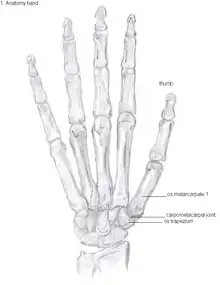

Trapeziometacarpal osteoarthritis (TMC OA) is, also known as osteoarthritis at the base of the thumb, thumb carpometacarpal osteoarthritis, basilar (or basal) joint arthritis, or as rhizarthrosis.[3][1][2] This joint is formed by the trapezium bone of the wrist and the metacarpal bone of the thumb. This is one of the joints where most humans develop osteoarthritis with age.[4] Osteoarthritis is age-related loss of the smooth surface of the bone where it moves against another bone (cartilage of the joint).[3][5] In reaction to the loss of cartilage, the bones thicken at the joint surface, resulting in subchondral sclerosis. Also, bony outgrowths, called osteophytes (also known as “bone spurs”), are formed at the joint margins.[6]

Anatomy

The TMC joint is a synovial joint between the trapezium bone of the wrist and the metacarpal bone at the base of the thumb. This joint is a so-called saddle joint (articulatio sellaris), unlike the CMC joints of the other four fingers which are ellipsoid joints.[17] This means that the surfaces of the TMC joint are both concave and convex.

This shape provides the TMC joint a wide range of motion. Movements include:[18]

The TMC joint is stabilized by 16 ligaments.[19] Of these ligaments, the deep anterior oblique ligament, also known as the palmar beak ligament, is considered to be the most important stabilizing ligament.[20]